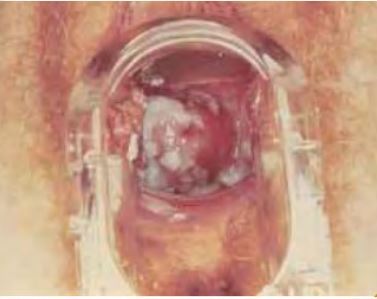

27a, HIV+ CCO: LSIL (lesao intra epitelial escamosa de baixo grau) 1. Qual a conduta frente a essa paciente? 2. De acordo com a imagem, qual o teste realizado, qual o achado e qual a conduta?

1. Convocar paciente para nova consulta o mais rapido possivel Solicitar Colposcopia 2. Teste de Shiller Teste de Shiller positivo ou lugol negativo Indicar biopsia da lesao